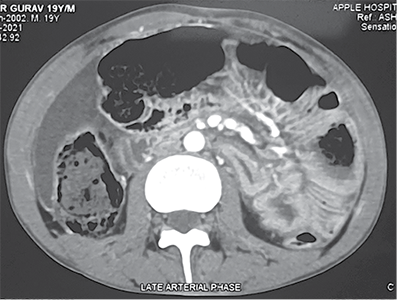

He was resuscitated with 1 500 ml of crystalloids through a left subclavian central line. Contrast-enhanced CT of the abdomen revealed perforation of the urinary bladder and extravasation of free urine into the pelvic cavity. It also revealed pneumointestinalis and grossly dilated bowel loops till mid transverse colon. There was a cut-off point at the level of the mid transverse colon (Figure 1).

Figure 1. Contrast enhanced computed tomography abdomen pelvis showing A – axial view showing dilated ascending colon, proximal transverse colon, intraperitoneal fluid collection B – extravasation of urine inside peritoneal cavity with pelvic collection